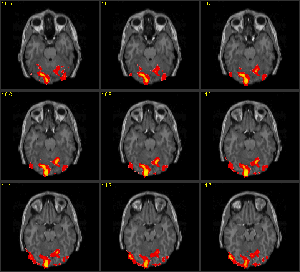

Hersenonderzoek is in een stroomversnelling gekomen met de beschikbaarheid van de MRI-scan voor niet-medisch personeel, de zgn fMRI (functionele Magnetic Resonance Imaging). Dat is iets anders dan gewone MRI. Een fMRI scanner laat geen anatomie zien, maar activiteit. Op een scherm kan de arts of wetenschapper zien in welk gebied de hersenen actief zijn. Deze lichten namelijk op. Op deze manier worden allerlei functies toegeschreven aan bepaalde gebieden. Als bijvoorbeeld een deel van de hersenen steeds oplicht als proefpersonen bang worden gemaakt, concluderen wetenschappers dat daar het angstcentrum zit.

Tegenwoordig leggen we iedereen onder de scanner, we laten hem of haar een cognitief taakje doen, of we laten hem naakte wijven zien, we laten hem of haar masturberen, copuleren met een tweede proefpersoon, verdriet hebben, lachen, huilen.. you name it. Allemaal in dat apparaat. En dan kijken we welk hersendeeltje rood of blauw oplicht en dan zeggen we: kijk nu toch eens aan, is dat niet geweldig? Als je masturbeert gaat precies hetzelfde lichtje aan als in situaties waarin je een compliment ontvangt van je collega. Weet je wat? Dat stukje noemen we ‘genotscentrum’. Dus masturberen en complimenten krijgen vinden we fijn, mensen. Kan iemand dat even noteren? We vinden dat fijn! Brekend!